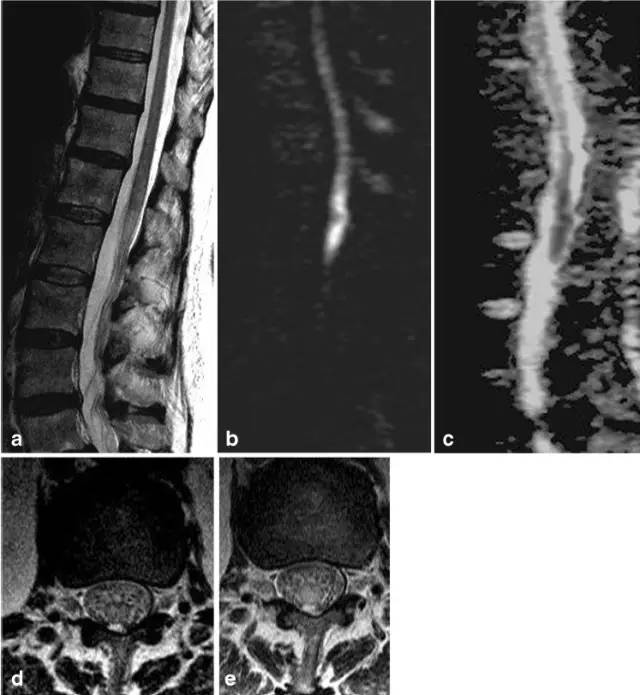

病例8:腰膨大和脊髓圆锥梗死。T2(图a矢状位,图d和e轴位)显示脊髓圆锥近完全横贯性高信号,T1可见轻微强化(图c)